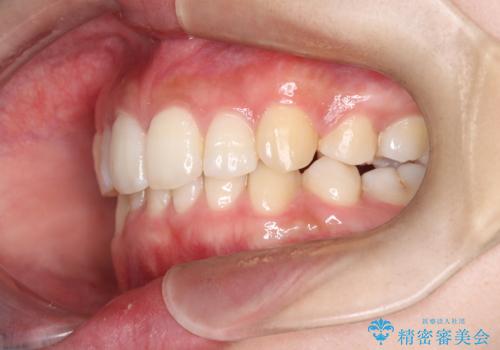

重度の歯のがたつきを、目立たない矯正と抜歯で根本改善

- 前歯から奥歯にかけて歯の重なりが激しい歯のがたつき(重度叢生)を主訴にご来院されました。精密検査の結果、歯が並ぶスペースが大幅に不足しており、歯並びを整え、口元を美しく引っ込めるためには、スペースの確保が必要と診断しました。そこで、上下左右の第一小臼歯(4番目の歯)を計4本抜歯し、そのスペースを利用して歯並び全体を整える抜歯矯正の治療計画を立案。装置には、透明で目立たないインビザラインを採用し、審美性と治療効果の両立を目指しました。

今回の治療では、重度の叢生を改善するため、まず計画通り上下左右4本の小臼歯を抜歯し、歯を並べるための十分なスペースを確保しました。装置には透明で取り外し可能なインビザラインを使用。抜歯によってできたスペースを最大限に活用し、マウスピースを定期的に交換しながら、デコボコを解消しつつ、前歯を効果的に後退させました。

治療の結果、長年の悩みであった重度の歯のがたつきが解消され、口元の突出感も改善。機能的にも安定し、審美的にも美しい、理想的な歯並びを獲得していただけました。